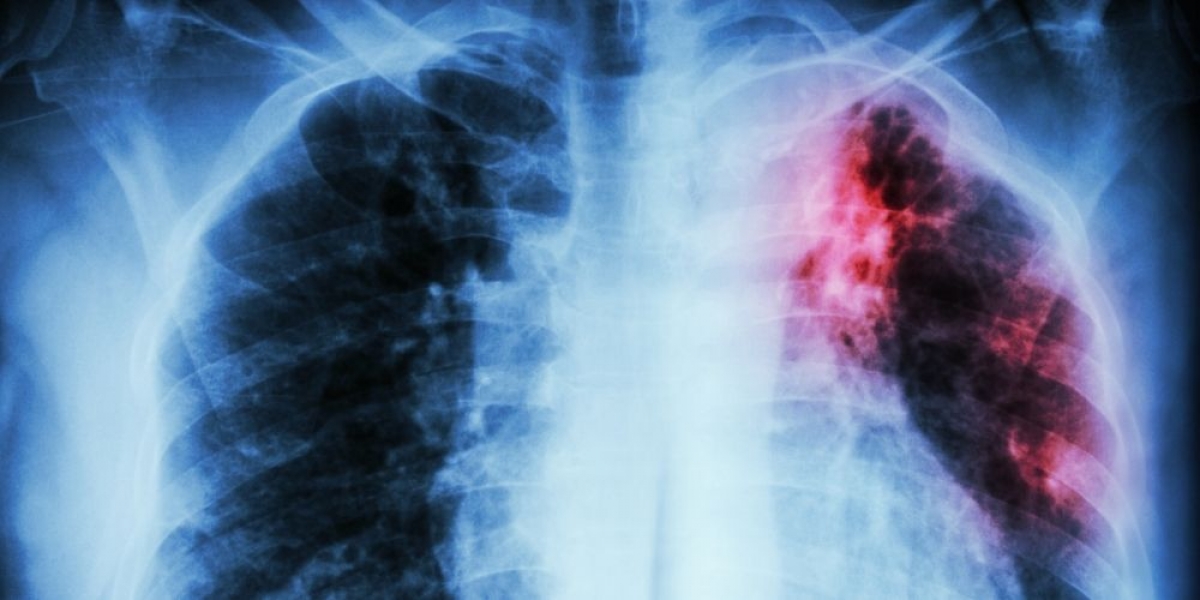

της Ελένης Ταυρίδου Τί είναι η Ιδιοπαθής Πνευμονική ίνωση; Η ιδιοπαθή πνευμονική ίνωση (IPF) είναι μια σοβαρή χρόνια ασθένεια που προσβάλλει τον ιστό που περιβάλλει τις κυψελίδες των πνευμόνων. Αυτή η κατάσταση εμφανίζεται όταν αυτός ο πνευμονικός ιστός γίνεται παχύς και άκαμπτος και καταλήγει να σχηματίζει ουλές εντός των πνευμόνων.…